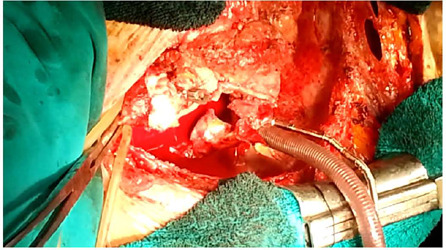

心脏手术后不久发生Stanford A型急性夹层的患者有很高的破裂和死亡风险。原发性升主动脉夹层(Stanford A型或De Bakey I型或II型)的表现、处理和结果都有很好的描述。然而,在心脏手术后不久(3-4周)发生Stanford A型急性主动脉夹层的患者有明显不同的表现、处理和术后结果。在本报告中,我们描述了一例早期Stanford a型急性主动脉夹层患者在初级冠状动脉搭桥术后四周的临床和手术表现。

Patients having Stanford type A acute dissection soon after cardiac surgery have a high risk of rupture and death. The presentation, management, and outcome of primary dissection of the ascending aorta (Stanford type A or De Bakey type I or II) are well described. However, patients with Stanford type A acute aortic dissection soon (3-4 weeks) after primary cardiac surgery have distinctly different presentation, management, and postoperative outcome. In this report, we describe the clinical and surgical findings of a patient with early Stanford type A acute aortic dissection four weeks after primary coronary artery bypass grafting.